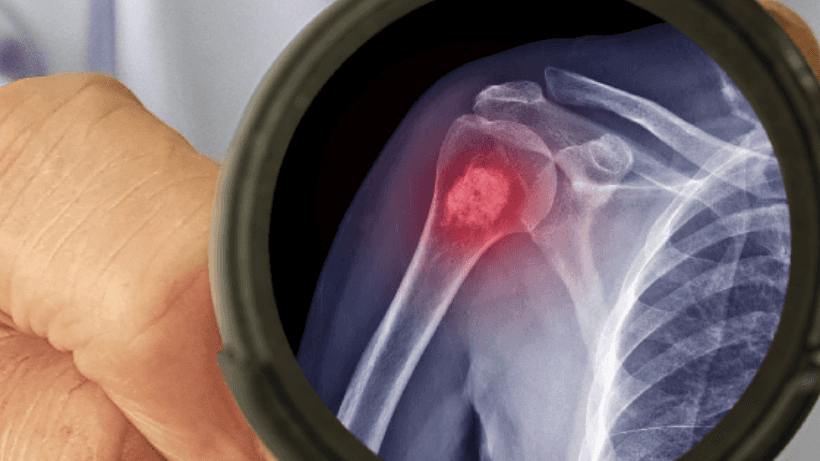

Paano nasuri ang kanser sa buto?

Kapag nakaranas ka ng mga sintomas atbisitahin ang isang doktor, Susuriin ka ng iyong doktor upang makilala ang problema at inirerekumenda ang iba't ibang mga pagsubok upang kumpirmahin ang diagnosis ng kanser sa buto tulad ng x-ray, pag-scan ng buto, mga biopsies ng buto, Mga CT scan, atbp.